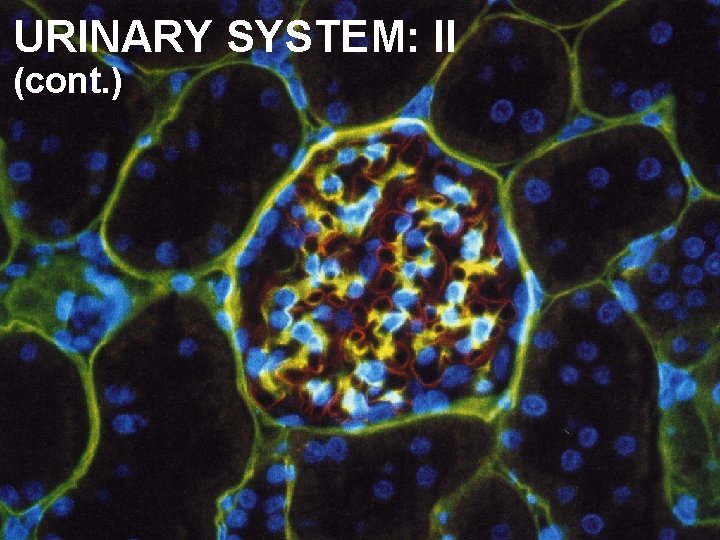

URINARY SYSTEM: II (cont. )